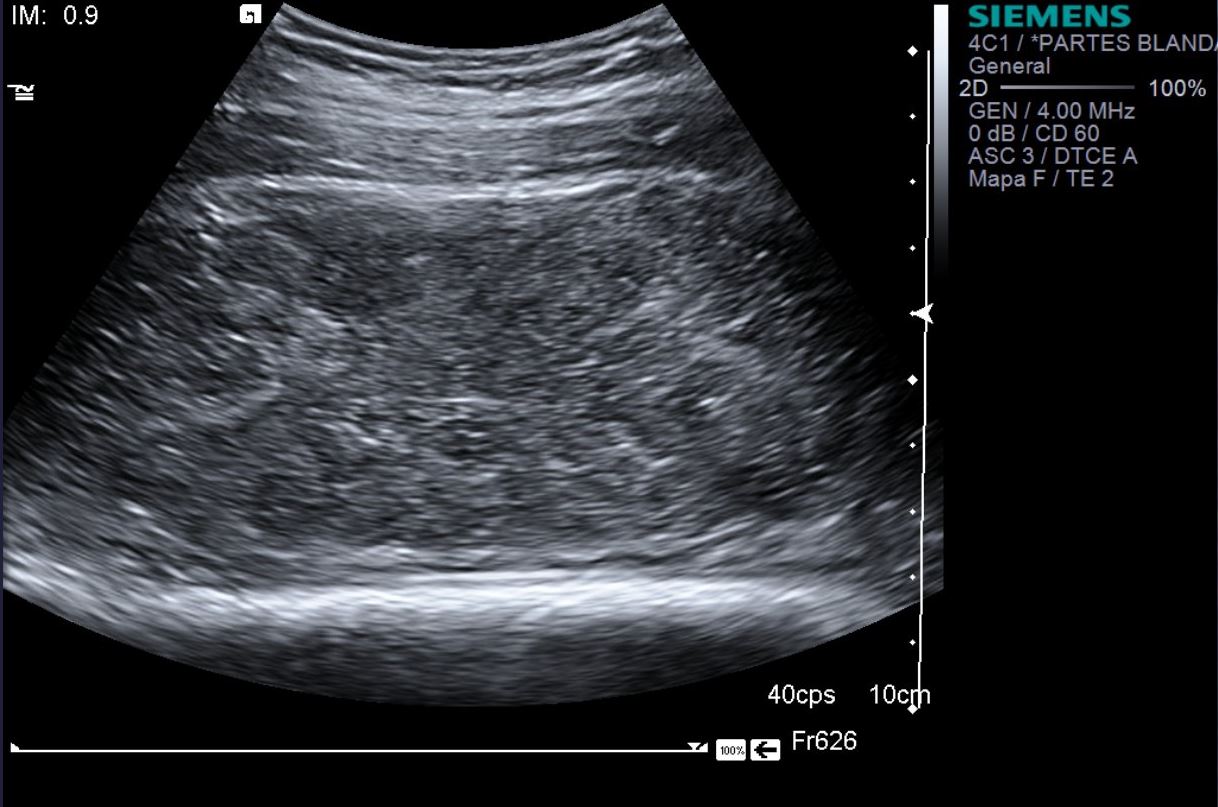

eco modo b